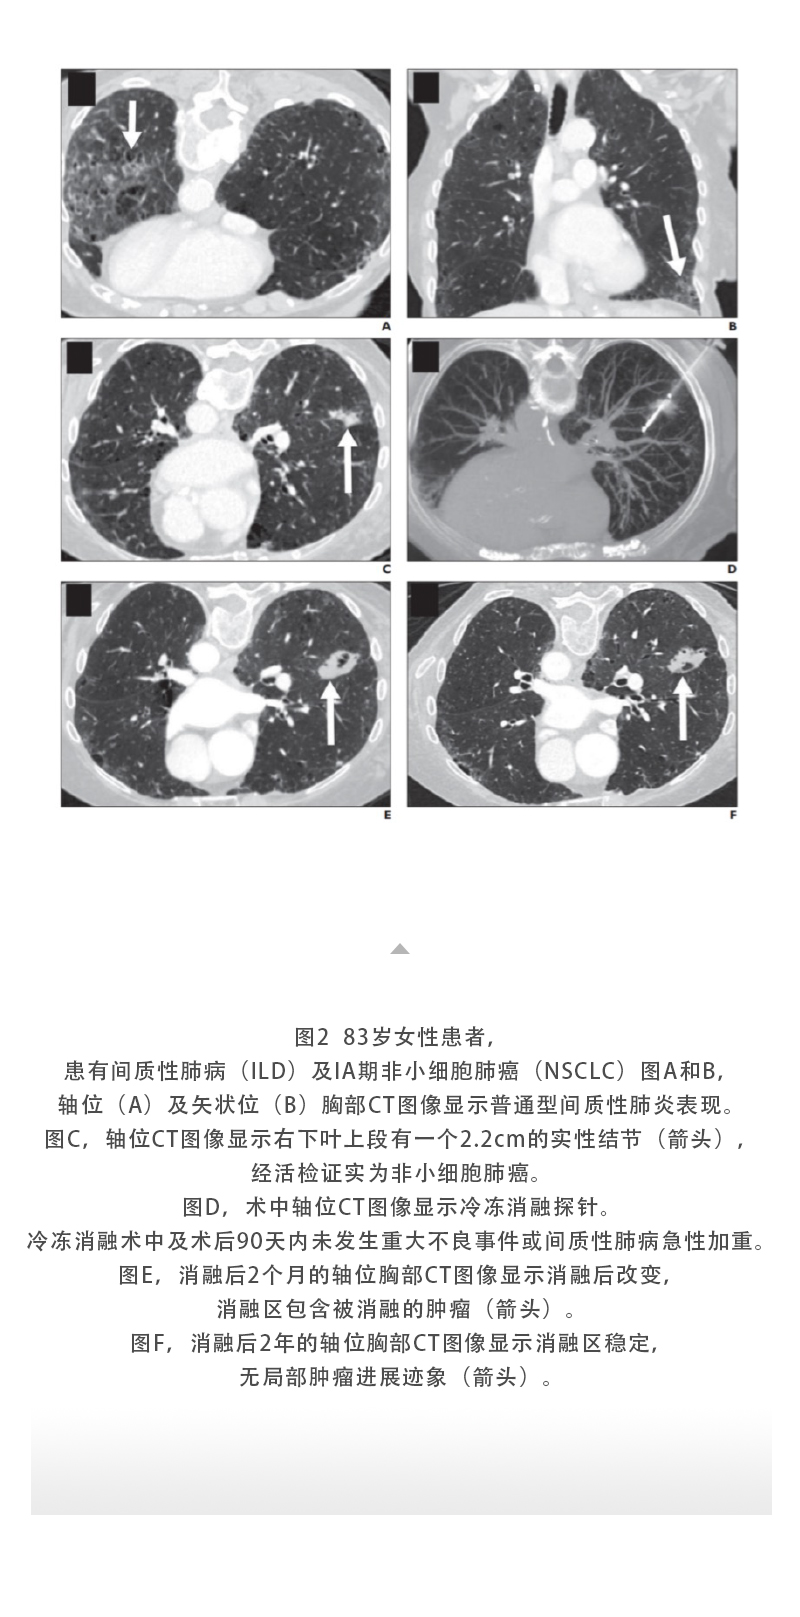

【HYGEA·科研資訊】肺癌冷凍消融